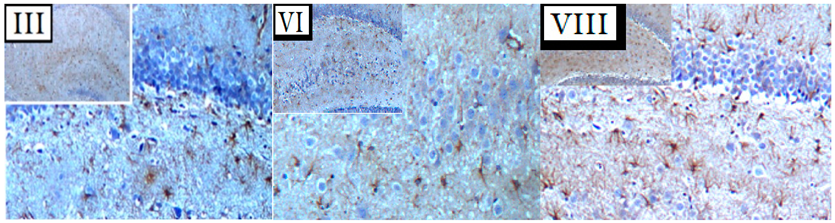

In the original publication [1], there was a mistake in Figure 8. During paper submission, in Figure 8A, a mismatch error in the (4×–10×) coronal sections of three panels, at the III, VI, and VIII treatment levels, took place. The new corrected treatment panels—III, VI, and VIII—for Figure 8A appear below. The authors state that the scientific conclusions are unaffected by the above error. This correction was approved by the Academic Editor. The original publication has also been updated.